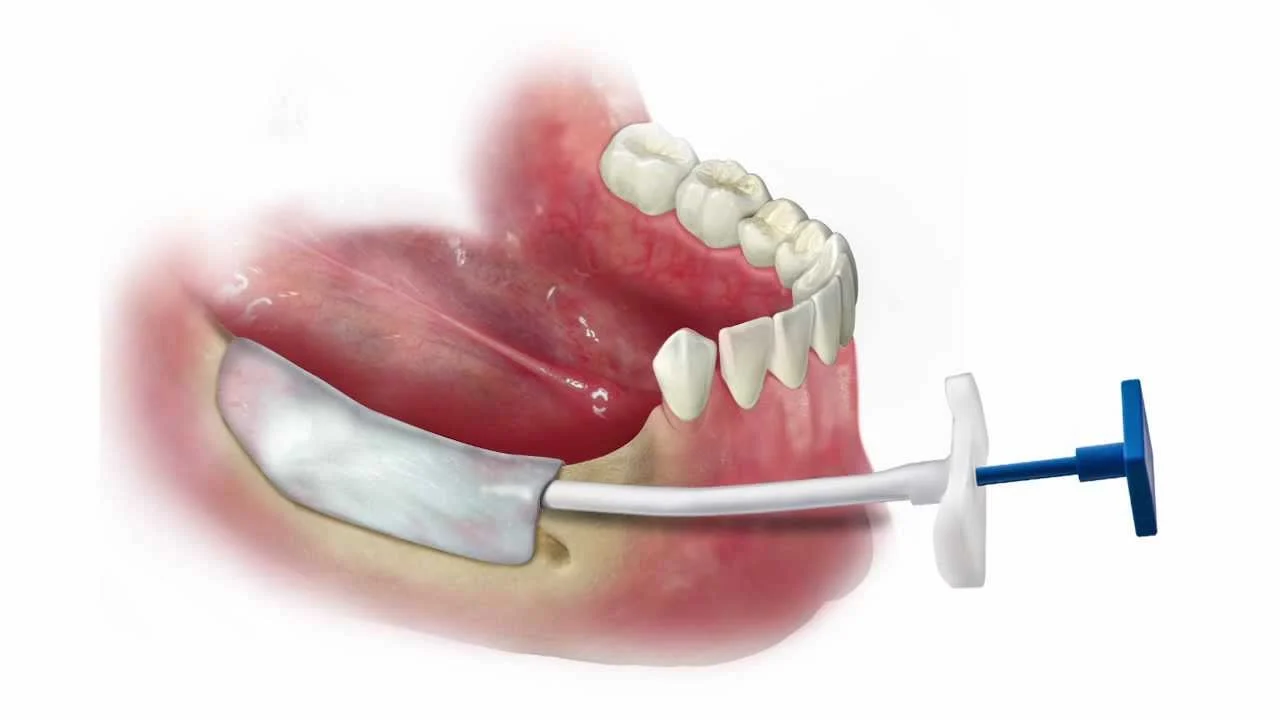

Descrizione dell’intervento: anestesia, tecniche usate, durata

- L’intervento viene generalmente eseguito in anestesia locale, ma nei casi complessi o in pazienti particolarmente ansiosi può essere utilizzata anche la sedazione cosciente.

- Si inizia con una piccola incisione nella gengiva per accedere all’osso sottostante. Una volta individuata l’area da trattare, si inserisce il materiale da innesto.

- Il materiale osseo viene inserito in forma di particelle o blocchetti, a seconda della tecnica. Viene poi protetto con una membrana (resorbibile o non resorbibile) che ne facilita la stabilità e l’attecchimento.

- L’intervento dura solitamente dai 45 minuti alle 2 ore, a seconda dell’area e della quantità di osso da rigenerare.